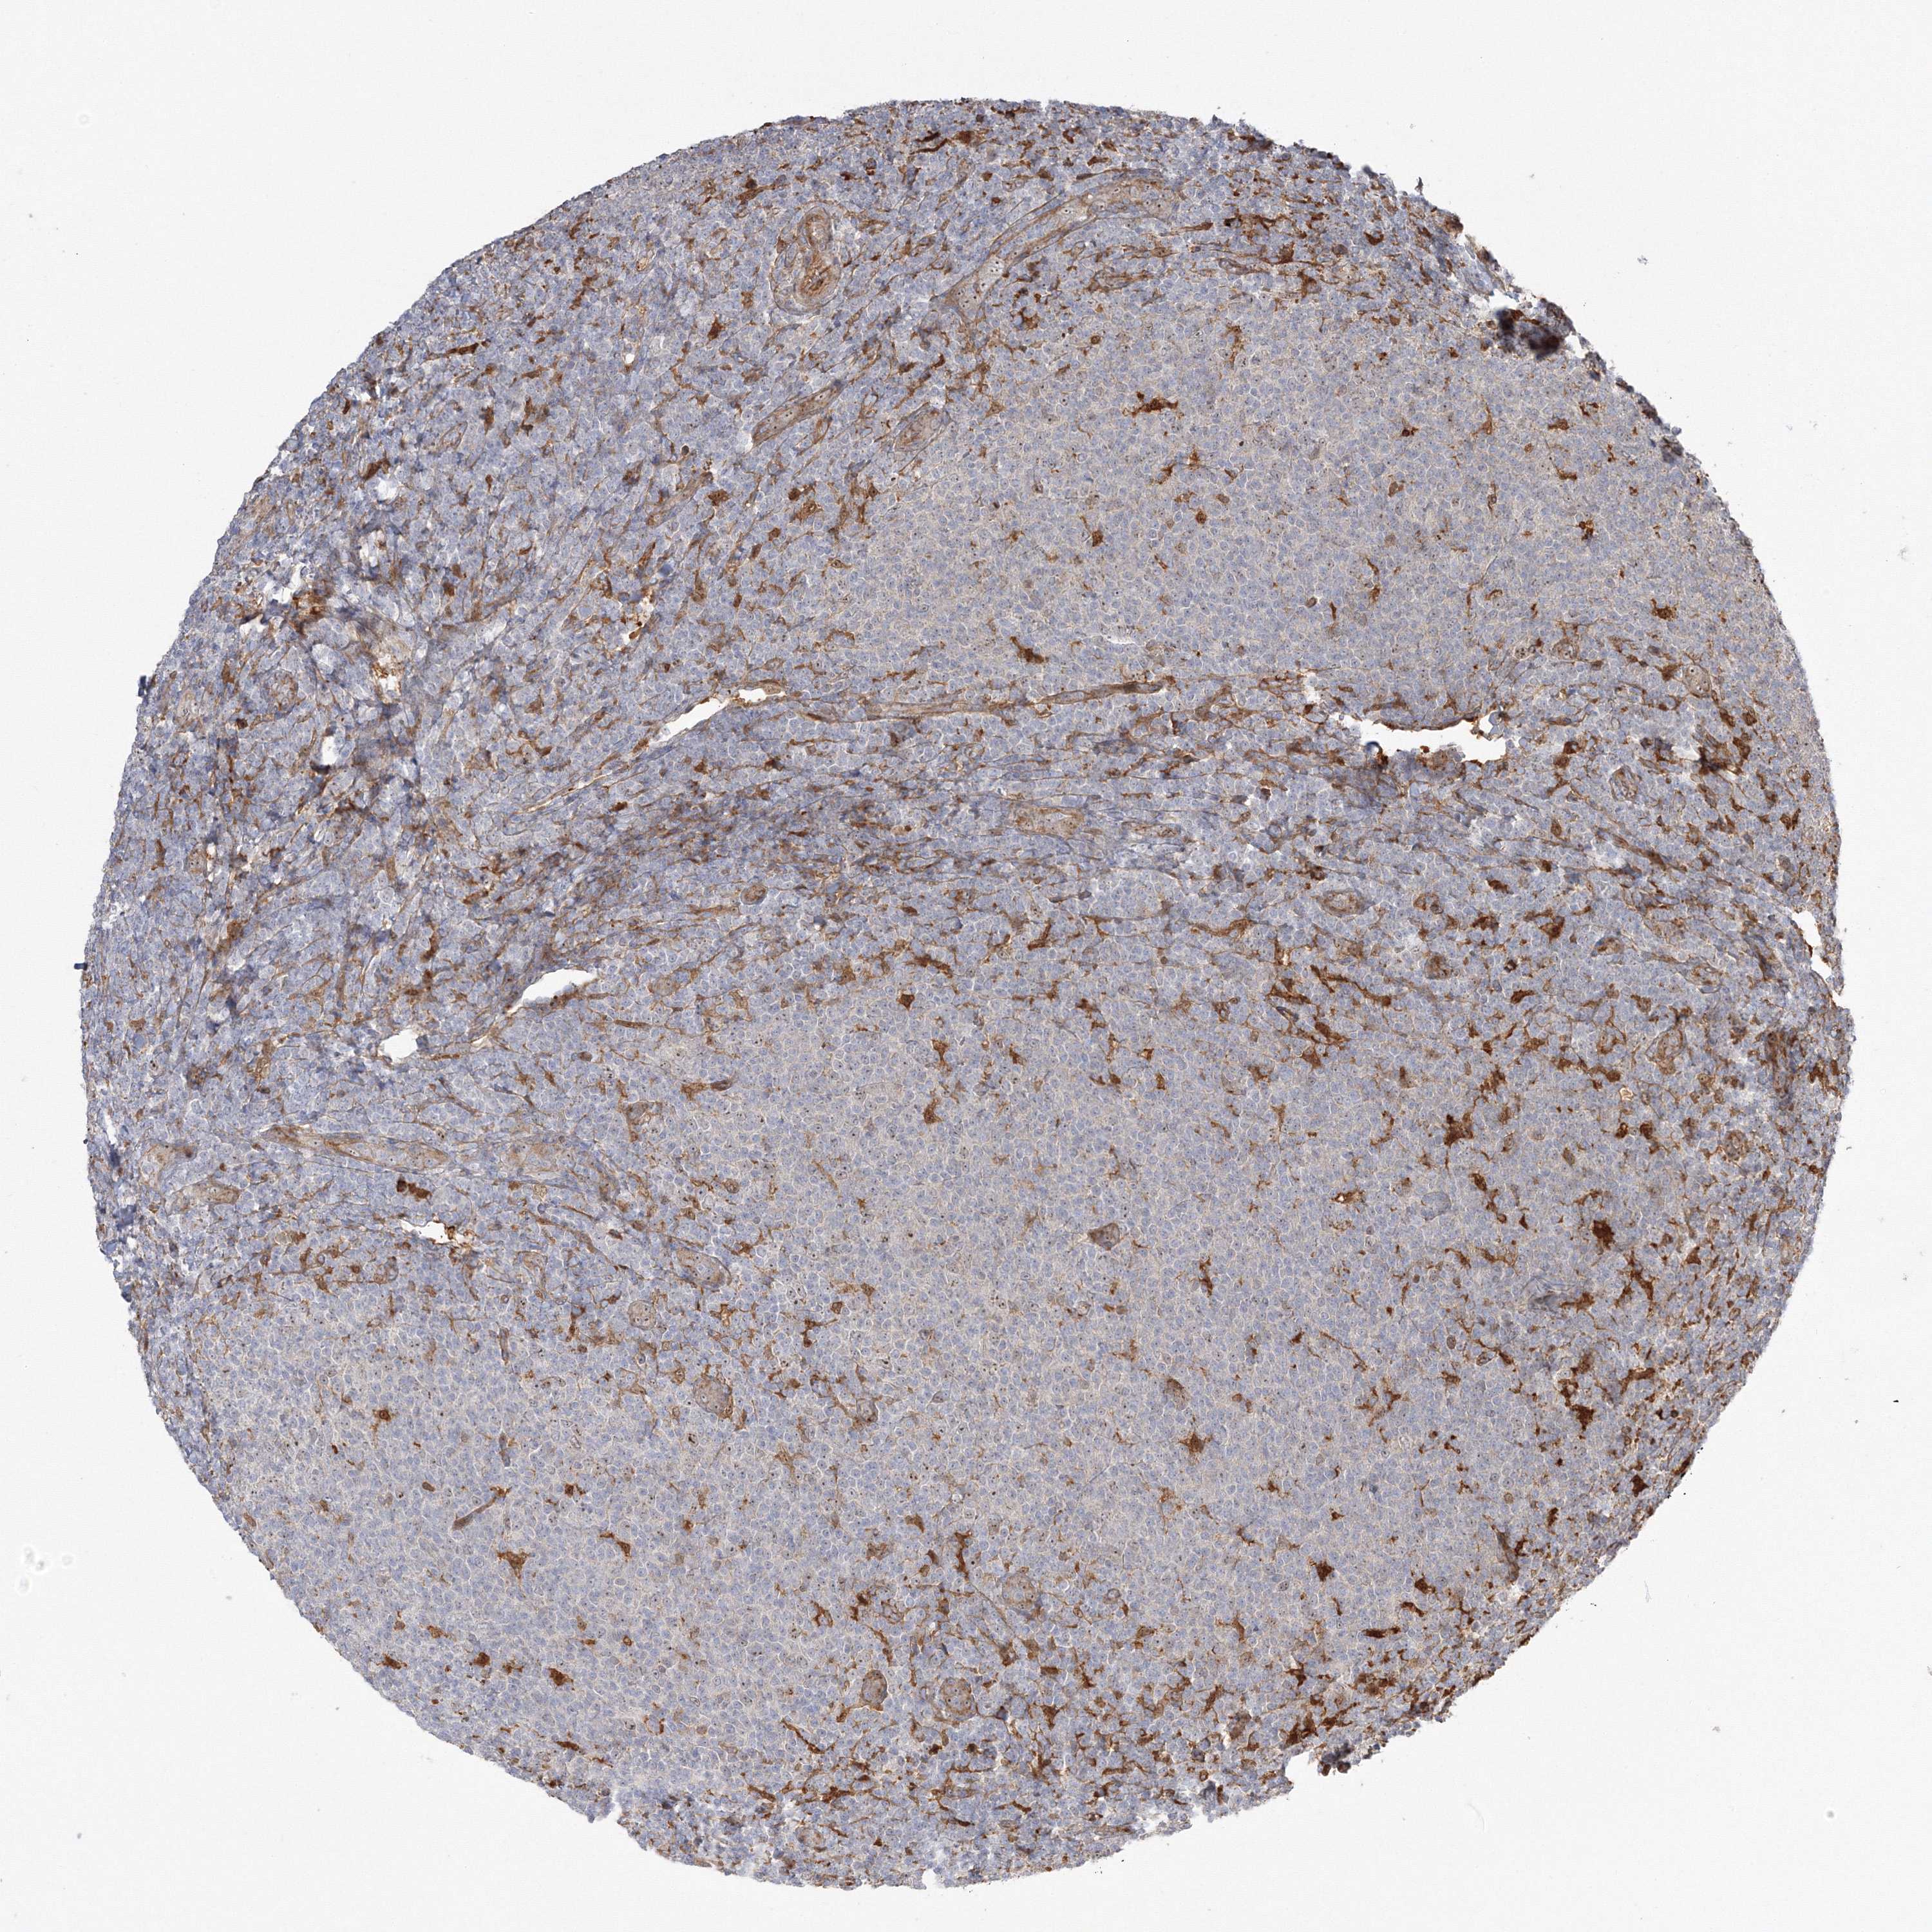

CANCER LYMPHOMA Show tissue menu

LYMPHOMA - Protein expressioni

A mouse-over function shows sample information and annotation data. Click on an image to view it in a full screen mode. Samples can be filtered based on level of antibody staining by selecting one or several of the following categories: high, medium, low and not detected. The assay and annotation is described here.

Antibody stainingi

Antibody staining in the annotated cell types in the current human tissue is reported as not detected, low, medium, or high, based on conventional immunohistochemistry profiling in selected tissues. This score is based on the combination of the staining intensity and fraction of stained cells.

Each image is clickable and will lead to virtual microscopy that enables deeper exploration of all samples and also displays staining intensity scores, fraction scores and subcellular localization as well as patient and tissue information for each sample.

Antibody HPA036295

Antibody HPA036296

Hodgkin's disease, NOS

Malignant lymphoma, non-Hodgkin's type, High grade

Malignant lymphoma, non-Hodgkin's type, Low grade